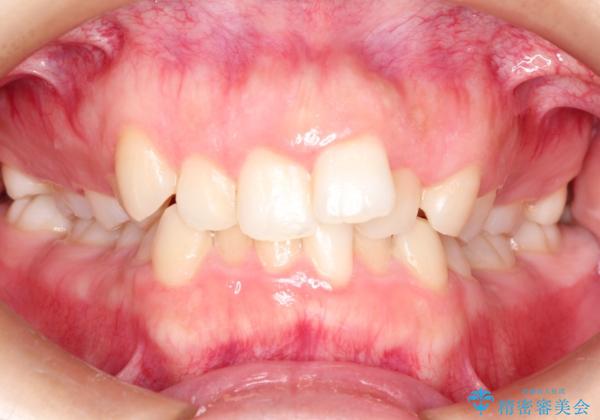

押しつぶされた歯列、アーチの拡大だけで非抜歯で改善した症例

- 前歯の歯並びの改善を希望され来院された患者様です。

初診時の歯並びの状態としては、上下ともに全体に及ぶの中等度以上のがたつき(叢生)があり、全額的に歯列のアーチが内側に押しつぶされた状態でした。

強い叢生がありましたが、抜歯は行わず上下顎ともに、主に歯列弓の拡大を行い叢生を改善しました。